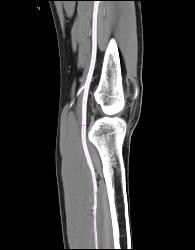

Patent Popliteal Artery and Trifurcation